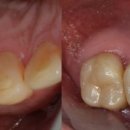

가장 정석적인 치료를 한다면 잇몸을 깨끗하게 관리하면서 교정을 하고 치아가 상실된 부위에 임플란트 또는 브릿지 치료를 하는 것입니다. 하지만 환자분께서는 교정치료를 하실 수 없는 상황이었고, 최소한의 보철로 최대한의 효과를 낼 수 있도록 치료 계획을 세웠습니다. 1. 먼저 심하게 흔들리는 앞니는 발치...

라고 후기를 남겨 주셨습니다. 보통 많은 분들이 얼굴을 올려도 된다고 말씀해 주시지만, 큰 변화가 있는 입 주변만 올렸는데요. 이번 포스팅의 주인공 사진을...네비게이션 임플란트 활용(짧은 기간, 최소 개수) 안녕하세요. 치과의사 민재홍입니다. 이번 포스팅은 심한 잇몸 염증(치주염)으로 인해 다수의 발치...

Dentistry, Combination ART & SCIENCE(2025-07-01 16:56:00)